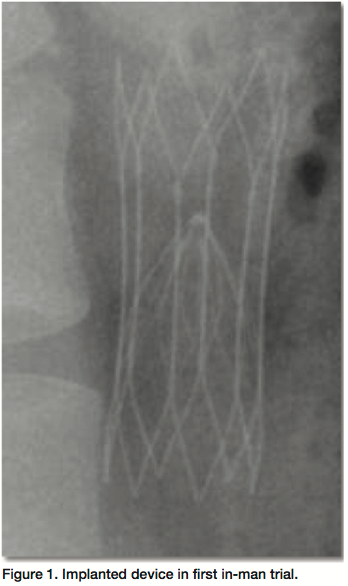

Not that we know of. The only thing we don’t know is the mechanism of how the filter of the device converts from a filter to stent-like configuration. The trial will soon start to show how well the filter functions. The study will evaluate accuracy of device placement, device transition from its filter to stent-like function, filter complications, and PE.

The animal trials were in sheep and we had no filter related complications. At necropsy, there were no PE to the lungs and all filters converted as planned.

I think we have 2 unique benefits. Number 1 is that this device offers protection from pulmonary embolism during the patient’s high-risk period, but avoids the necessity to retrieve the vena caval filter, which is an invasive procedure that has its own inherent risks and costs. There’s evidence that leaving a filter in the vena cava over the long-term increases the incidence of deep vein thrombosis. This is also avoided as the device converts from a filter to a stent and the vena cava remains widely patent as the device is endothelialized.